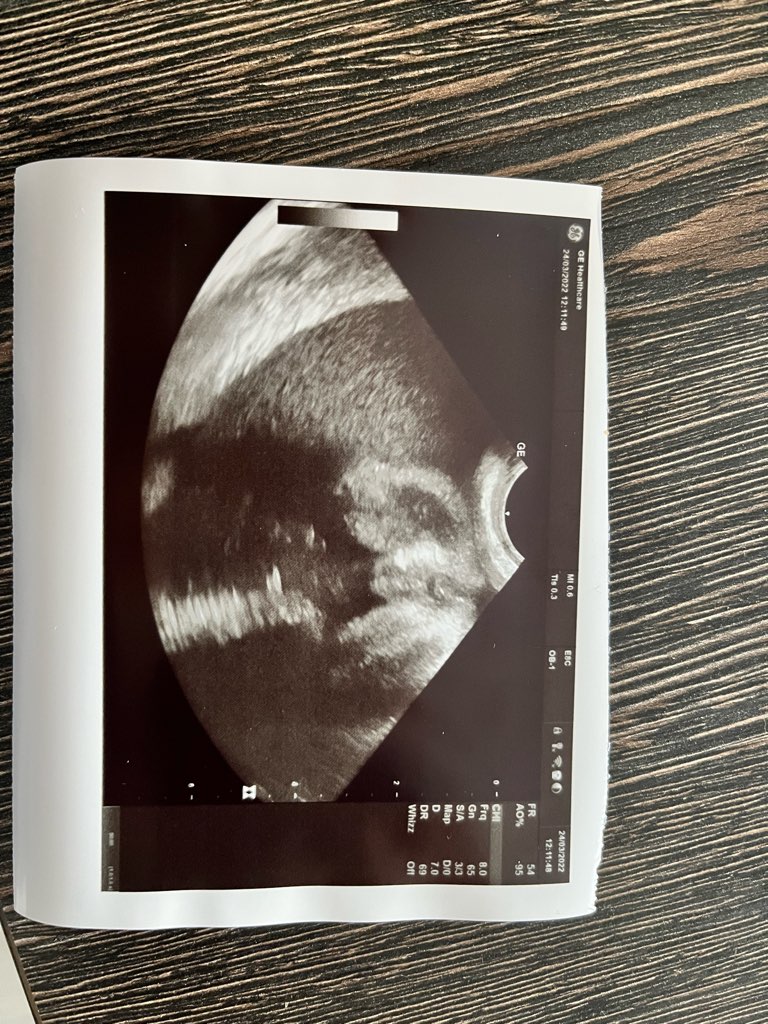

Dziewczynka czy chłopiec???

Witam 😁 jak myślicie kogo tu widać?

Na zdjęciu widać jakby dziecko siedziało w sensie od pośladki od spodu.

22tc+6dni

Powiedziała że na ten moment 90% że dziewczynka 🙈 ale zostawia sobie 10% na pomyłkę i że sprzęt nie taki super nowy i że może jeśli to chłopiec to mu się jajka ściągnęły.

Ogólnie jeszcze będę szła na prenatalne w 30tc i mam nadzieje że w 100% uda się powiedzieć że to dziewczynka. Bo niby jestem pewna i sama to czuje odkąd tylko dowiedziałam się o ciąży że to dziewczynka ale słyszałam o tylu pomyłkach lekarzy że aż się boje nawet pomimo tego że widzę że jajek i reszty brak 🙈